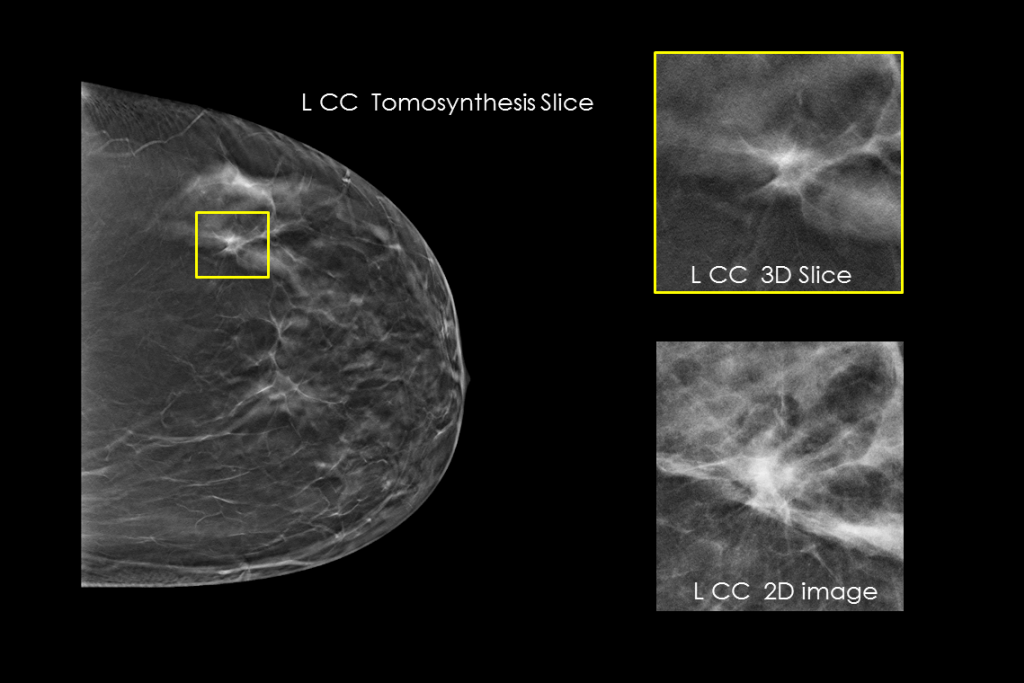

The Selenia Dimensions system delivers proven accuracy of our 3D Mammography exam to detect significantly more invasive breast cancers earlier and reduce call backs vs 2D alone.2-6,*

Diagnose Challenging Patients with Greater Certainty

Clinical Images